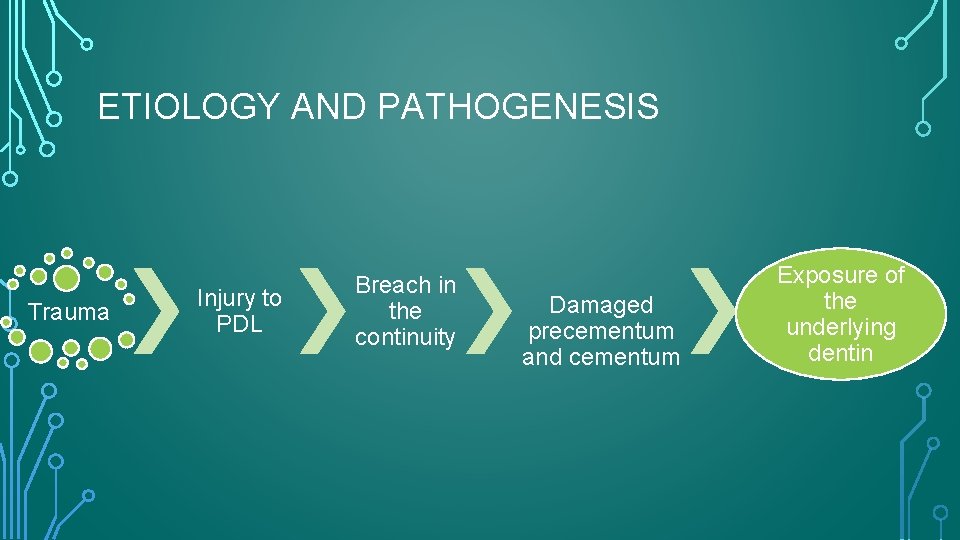

ETIOLOGY AND PATHOGENESIS Trauma Injury to PDL Breach in the continuity Damaged precementum and cementum Exposure of the underlying dentin